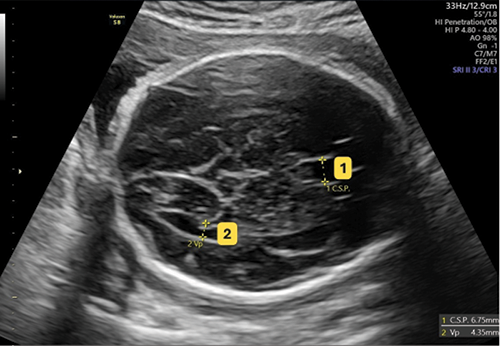

Comparative Analysis of Fetal Brain Structures in Gestational Diabetes versus Normal Pregnancy: A Prospective Cohort Study

Kamonchanok Choosak, MD¹, Podjanee Phadungkiatwattana, MD¹

140